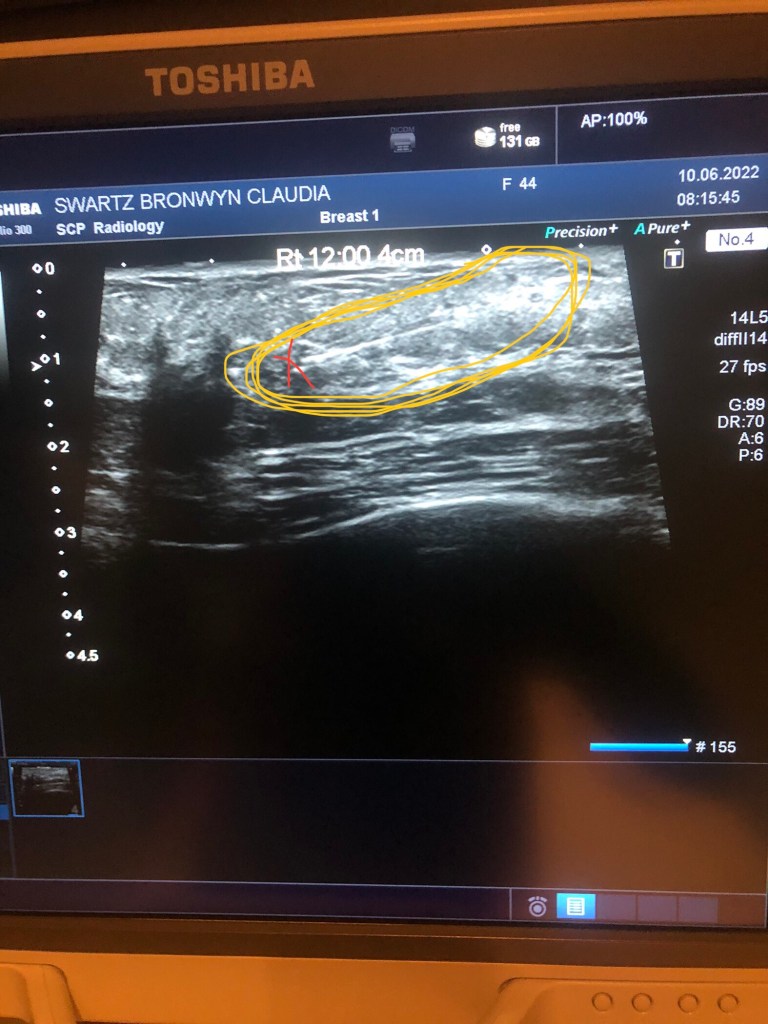

Thus, on the morning of the op, after being admitted I was taken to the radiology department where they performed an ultrasound. Using the ultrasound they inserted a guide wire to the site of the tumor where they ‘hooked it’. The purpose of this was to quickly direct the surgeon during surgery, to the piece of tissue that needed to be excised.